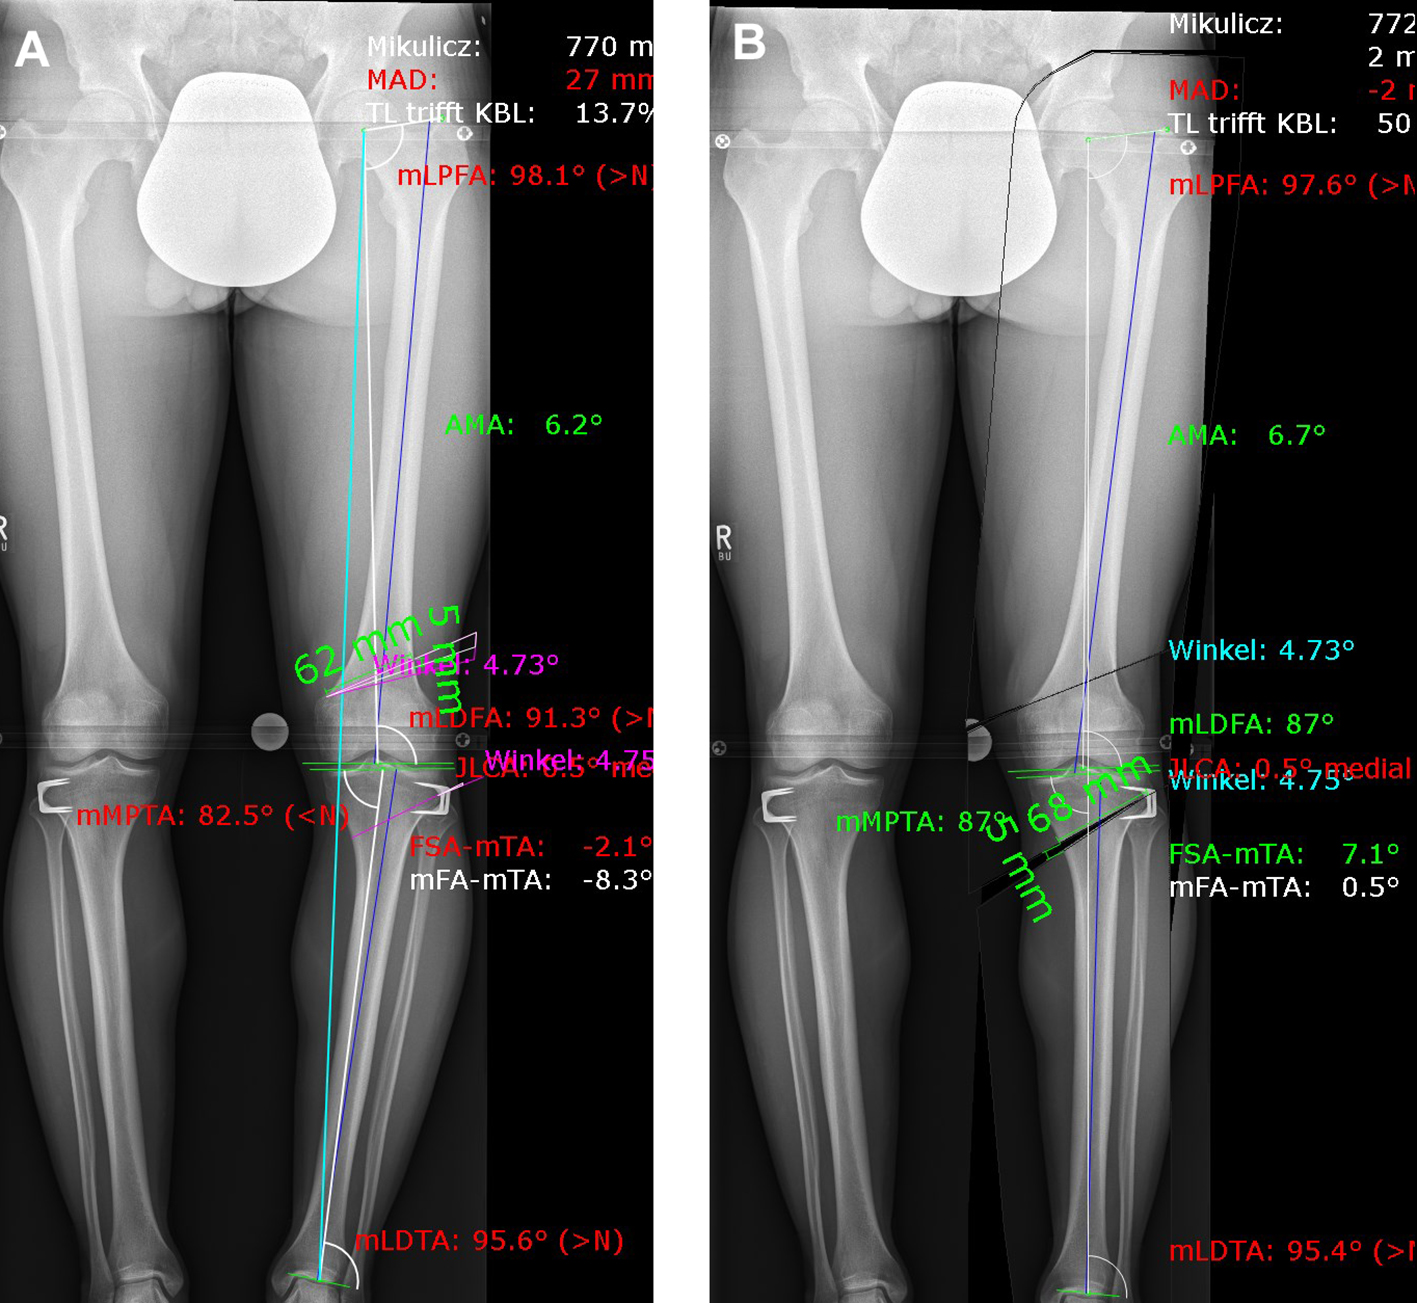

A patient presented with a congenital varus malalignment and complained of medial knee pain following epiphysiodesis at the proximal tibia. The MRI showed no cartilage lesion. A varus deformity of -8 in conjunction with medial knee pain was the indication for surgery. Fig 8 presents the deformity analysis of the left knee. Because of the deformity in the distal femur and proximal tibia, a double level osteotomy was planned and digitally simulated. The image on the left shows a combined deformity comprising a mechanical tibiofemoral angle (mTFA) of -8, a mechanical lateral distal femur angle (mLDFA) of 91, and a mechanical medial tibia angle (MPTA) of 83 (A). The image on the right shows the simulation of a double level osteotomy (B). Aim was a mTFA of 1 (valgus), a mLDFA of 87, and a MPTA of 87. The distal femur osteotomy was planned as a closed wedge distal femoral osteotomy (DFO) and the tibia osteotomy was planned as an open wedge HTO.